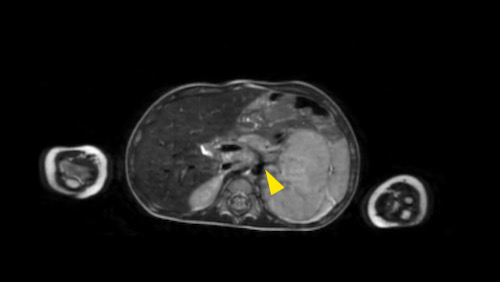

Đây là hình ảnh T1W axial có tiêm gadolinium với kỹ thuật xóa mỡ.

Hình ảnh cho thấy sự bao bọc của các mạch máu.

Lưu ý sự lan rộng của khối u ra phía sau động mạch chủ, đẩy động mạch chủ ra xa cột sống (mũi tên).